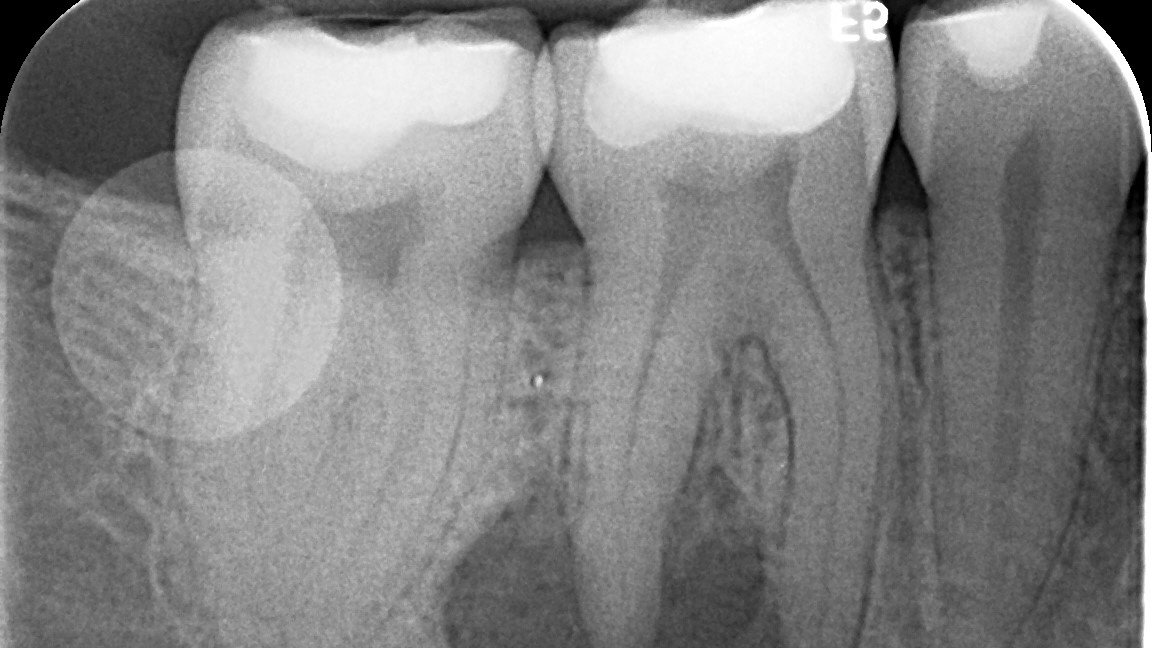

Various clinical presentations and risk factors can influence endodontic success or failure, including but not limited to the quality of the root canal performed and the seal of the coronal restoration.2 In addition to the aforementioned factors, the presence and size of a periapical lesion can directly affect the prognosis and treatment outcome. Classic literature highlights this shift in long-term success rates from 96% for vital/nonvital cases without the presence of a periapical lesion to 86% when a periapical lesion is present.3

Periapical radiographs have been commonly used to evaluate the size of periapical lesions. However, periapical radiographs have limitations, because the information is rendered in only two dimensions. A periapical lesion can only be detected in the radiograph when the mineral loss of bone reaches 30%–50%.4